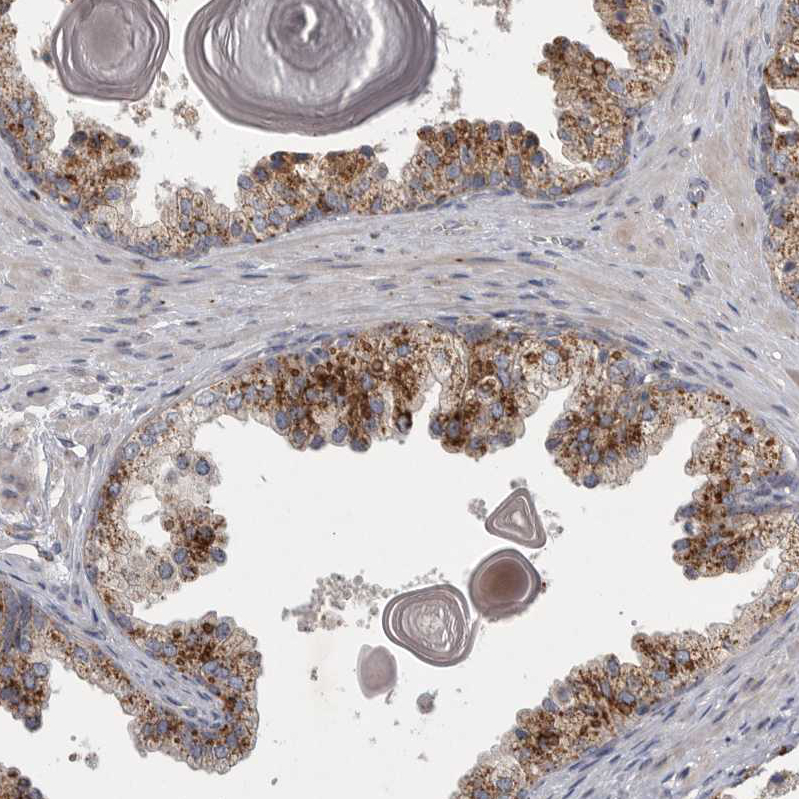

Immunohistochemical staining of human kidney shows strong cytoplasmic granular positivity in cells in tubules.